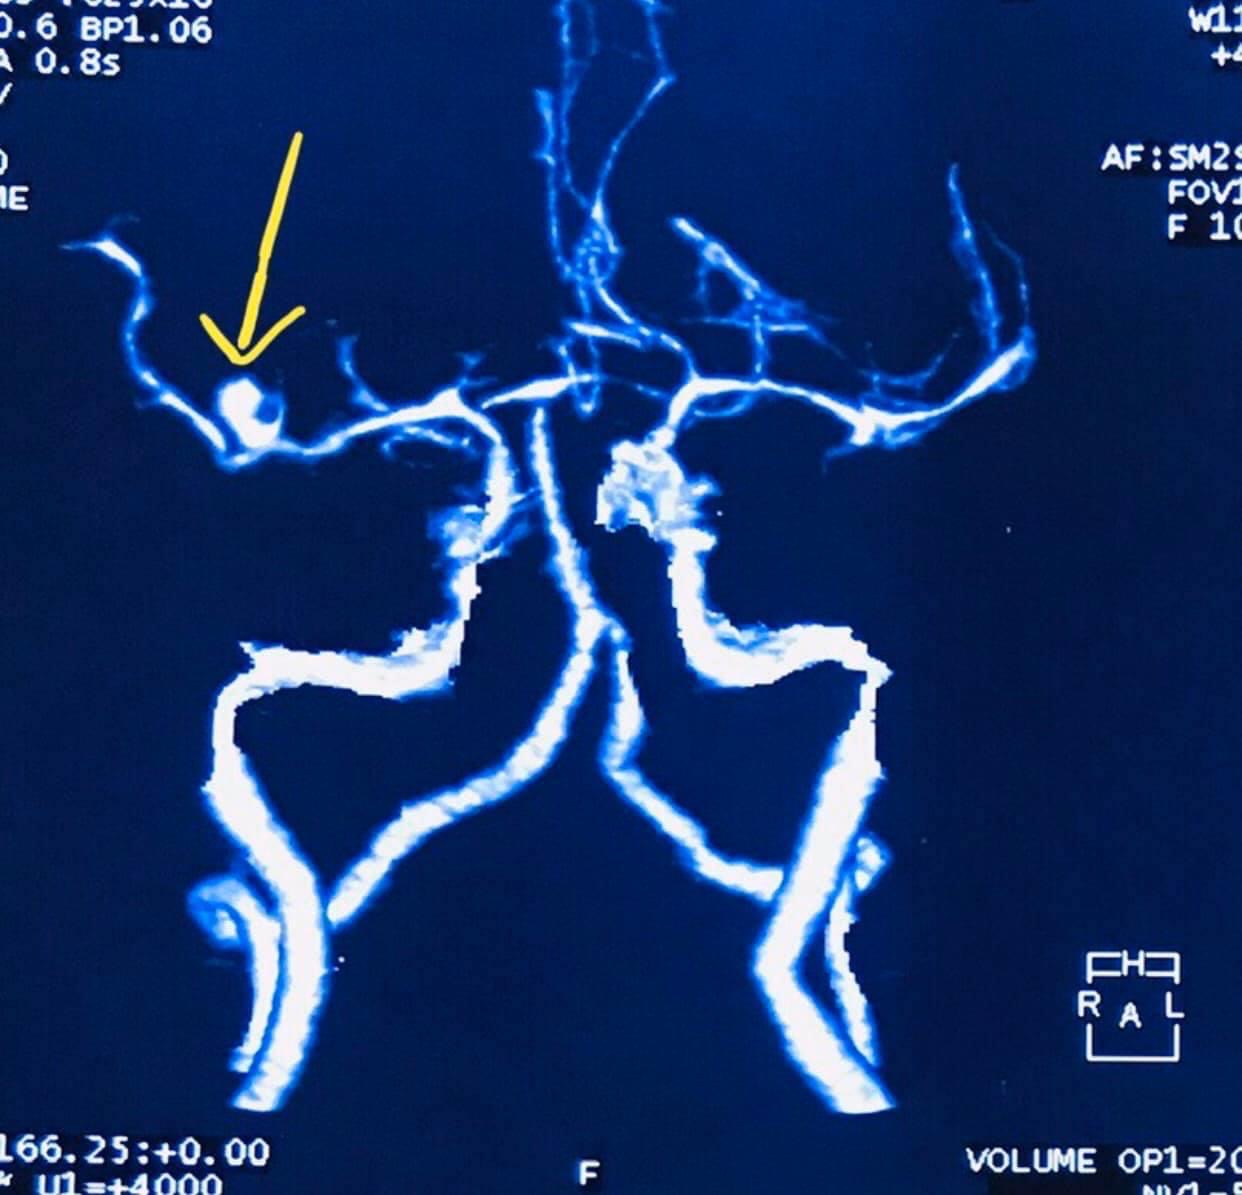

- Clip ligation of brain aneurysms (open microsurgery)

CT scan and/or MRI films or CDs must be brought including pertinent laboratory results/ medical records in order for us to provide you with a sound neurosurgical assessment.